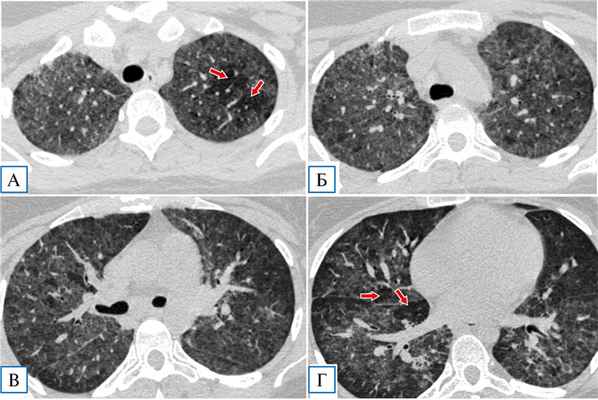

При компьютерной томографии органов грудной полости выявлены распространенные субтотальные зоны «матового стекла», в верхних отделах на фоне наиболее интенсивных зон — «воздушные ловушки»: первоначально КТ-картина расценена как проявления двусторонней вирусной пневмонии (КТ3/4) (рис. 1).

Рис. 1. Пациентка Я., 29 лет: компьютерная томография грудной клетки в день госпитализации

Примечание. Диффузные сливные зоны «матового стекла», почти равномерно распределенные как в верхних (А, Б), так и в нижних отделах легких (В, Г), на фоне которых визуализируются участки повышенной прозрачности — «воздушные ловушки» (показаны стрелками на А и Г).